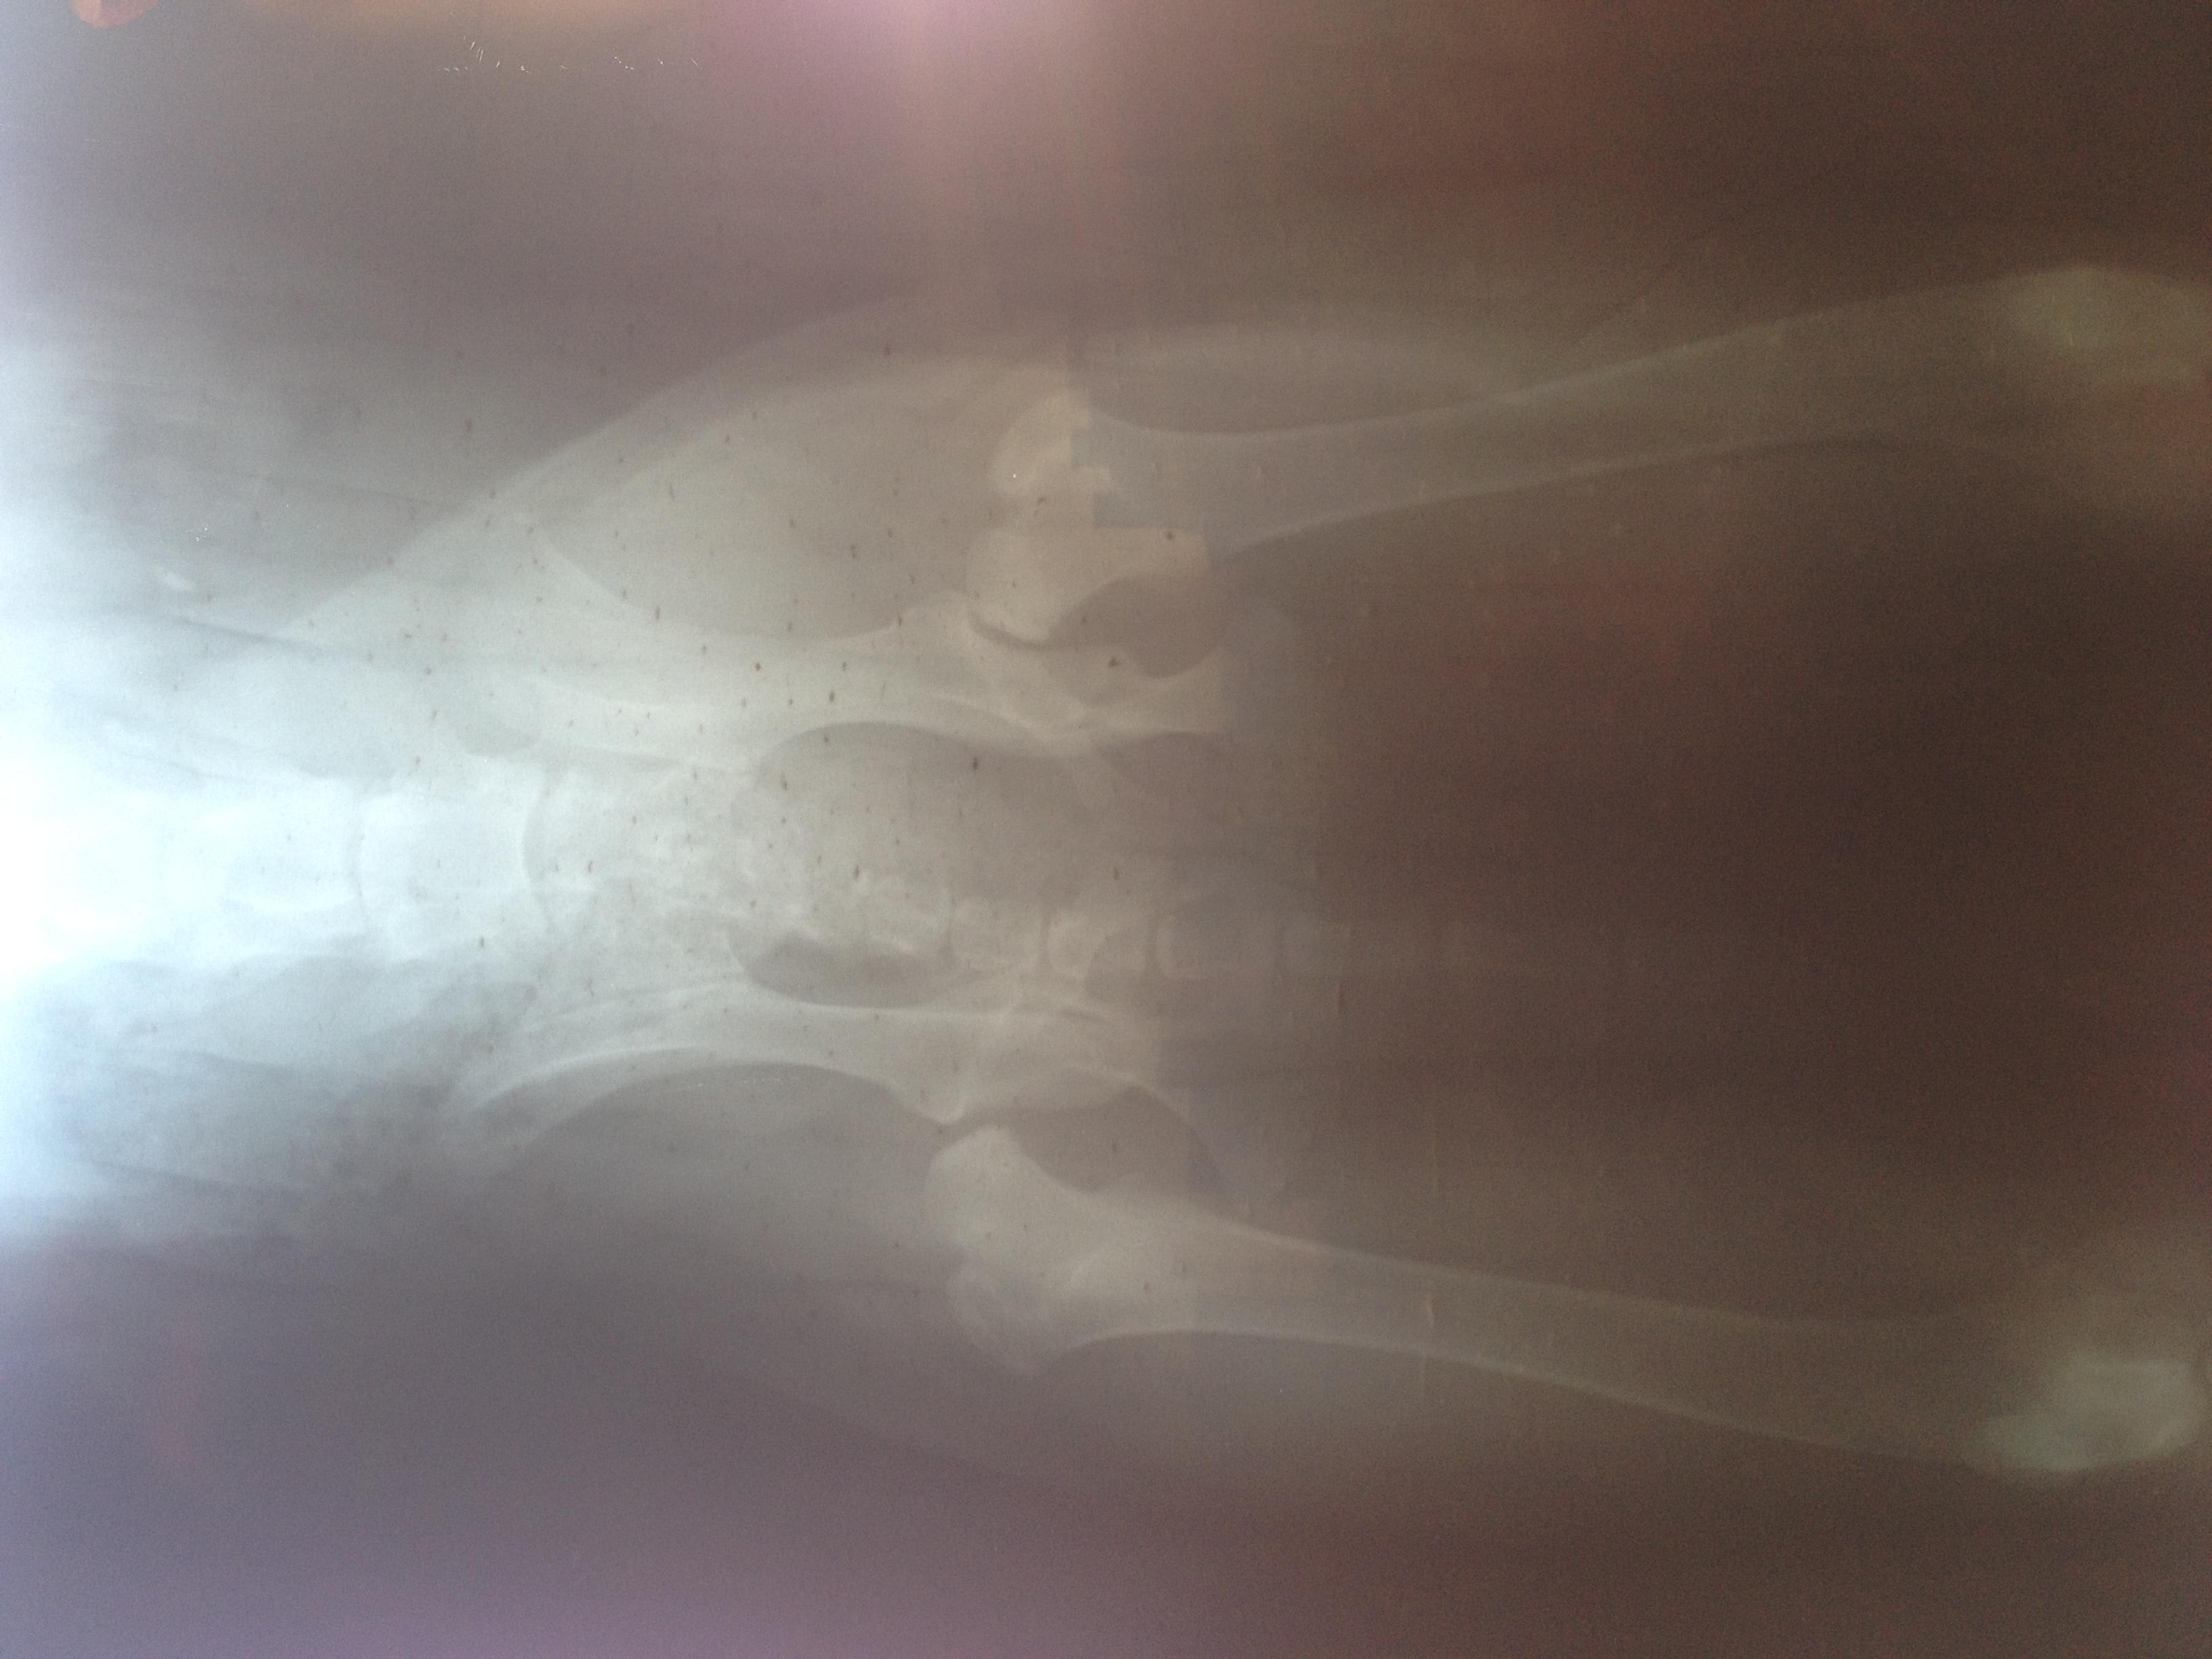

Dear Doctor , I have a puppy 7 month old ,cane Corso (Italian mastiff ) till three month old the way she walking was kind of strange the back legs movement looked awkward ( moving up stairs 5 steps as max ,like a bunny) now as I mentioned she is 7month old &I think she moved with the left back leg 2weeks ago more awkwardly ,so I decided to make her X-Ray and the doctor told me this is Hip dysplisia type E. Question : I can't afford operation ,if I left the dog as it is ,how would it be later?

Hello, thank you using Petco Pet Education Center, formerly Petcoach. I am so sorry for your concerns about Madiidda. Her x-rays show very severe subluxation of the one hip, & a very shallow acetabulum of the other. This will never get better on its own, & as she ages, she will experience more & more pain possibly to the point where she may no longer be able to walk. A lot has to do with how you manage her growth, weight, exercise/conditioning, and use of joint supplements & pain medications. You may not be able to afford the surgery now, but perhaps in a couple of years, you might be able to. The important thing is to keep her a tad underweight, regular gentle exercise, & start her on a good glucosamine/chondroitin sulfate supplement. Omega fatty acids can be of some benefit in helping the inflammation in her hips. Work closely with your veterinarian about weight control, medications, & possibly even a veterinarian who practices some alternative modalities such as acupuncture & massage therapy. Here in the US, we even have specialists in canine rehabilitation medicine, where underwater treadmills, water therapy, & special balance exercises can all help to strengthen the muscles around the hips to make life better for Madidda. I wish you all the best that she does well. She is a beautiful girl.